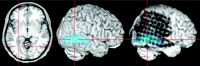

Fig 2.

The resulting skull-stripped postimplantation image is visualized within MRIcro. A simultaneous examination of the skull-stripped preimplantation and postimplantation 3D MR images in two yoked MRIcro application windows gives an excellent overview of the exact location of each electrode contact. The viewer is able to grasp the electrodes’ spatial relation to the sulcal pattern of the brain and to anatomic landmarks (e.g., the central sulcus as pointed out here by the crosshairs).